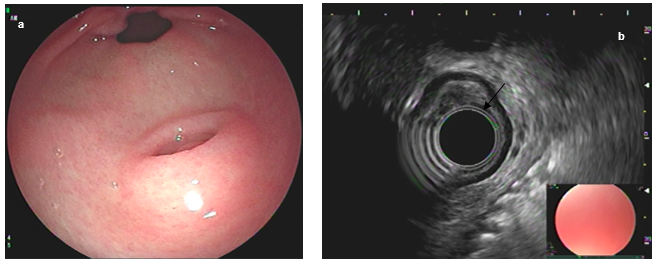

The average size was 11mm (range 5-19 mm) and the typical endosonographic pattern in “salt and pepper” was identified in all cases, as was the presence of an anechoic tubular structure (duct). Figure 2.

Figure 2. Antral ectopic pancreas (a). Endosonographic appearance (b), anechoic tubular structure, duct (arrow)